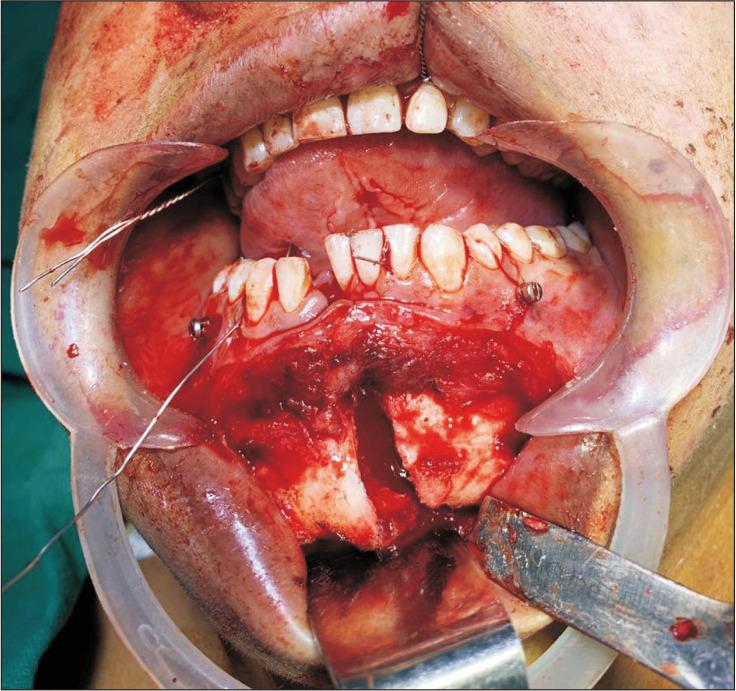

ATOM技术:使用螺钉-钢丝牵引进行解剖复位以切开复位内固定下颌骨骨折。

ATOM technique: Anatomic reduction using screw-wire Traction for Open reduction and internal fixation of Mandibular fractures.

Various techniques are well documented to obtain anatomic reduction, such as reduction forceps, manual reduction, or a combination of these methods. However, these techniques have inherent drawbacks. We propose a new intra-operative technique for anatomic reduction using screw-wire traction for open reduction and internal fixation of mandibular fractures.

摘要

有多种技术已被充分记录用于实现解剖复位,例如复位钳、手法复位或这些方法的组合。然而,这些技术存在固有缺陷。我们提出一种新的术中技术,即使用螺钉-钢丝牵引进行下颌骨骨折切开复位内固定的解剖复位。